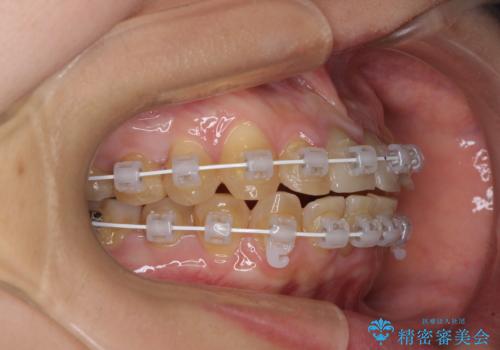

- 矯正装置

- 審美装置

- 治療期間

- 3年2ヶ月

抜歯矯正により口元を引っ込めることも検討しましたが、特に口元の突出感は気になっていないとのことで、非抜歯にてワイヤー装置で矯正治療を行うこととしました。